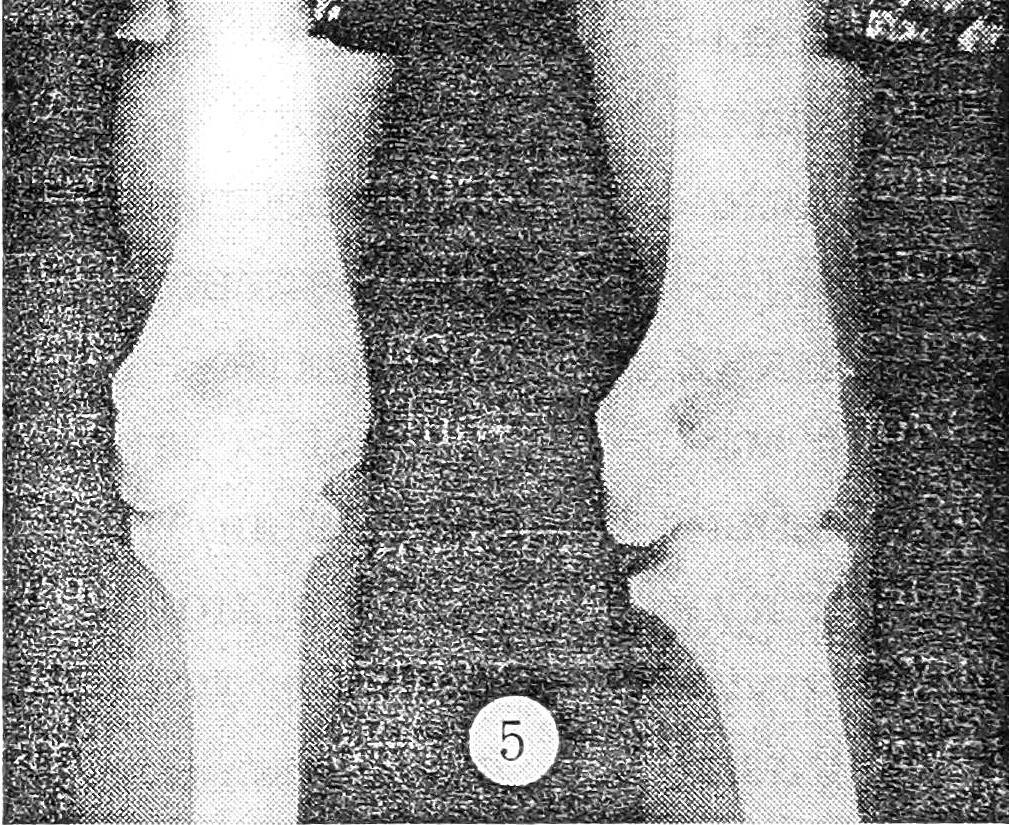

II | То же | Предплечье пассивно отводится на 10°, атрофия мышц плеча (2 см) и предплечья (1 см) | Ширина внутреннего отдела суставной щели в больном суставе в 2 раза больше, чем в здоровом (рис. 5) | Увеличение полости сустава или нарушение ее герметичности по внутренней поверхности сустава (рис. 6) | 19 |

Рис. 5. Рентгенограмма левого локтевого сустава, выполненная в специальной укладке: нестабильность II степени.